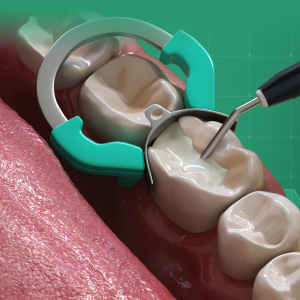

Materials and Techniques to Improve Class II Composite Restorations

Wednesday, June 26, 2019

Every day in dental practices all over the world, dental professionals complete one of the most common dental restorations: Class II direct composite restorations. However, Class II direct composite restorations can present numerous challenges. This article will cover Class II composite restorations...

Improve Class II Outcomes at Every Stage

Monday, August 29, 2016

Class II restorations are one of the most important aspects of practice growth due to the direct role they play in patient satisfaction. This eBook examines material advances that make your posterior composite procedures faster, easier, and more profitable, without compromising clinical outcomes.